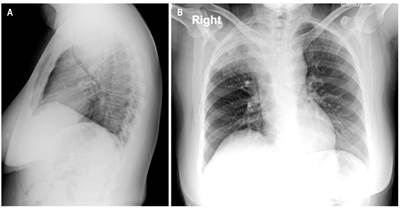

Se presenta el caso de una paciente femenina de 38 años con cuadro clínico consistente en disfagia de 1 año de evolución asociado con episodios ocasionales de hematemesis, por lo que se realizó una endoscopia de vías digestivas altas que evidenció una lesión endoluminal, friable e irregular que se localizó a 27 cm desde la arcada dentaria y de 12 cm de longitud, de la que se tomó una muestra para estudio histopatológico, que reportó una lesión benigna compatible con leiomioma. Sin embargo, se amplió el estudio con una TAC de tórax contrastada en la que se observó una masa tumoral a nivel del esófago cervical de 128 mm x 66 mm x 84 en diámetros L x AP x T, que se extiende hasta el esófago torácico transmural, exofítica, con realce homogéneo dependiente de la pared anterior la cual condiciona la obstrucción de la luz y ejerce un efecto de masa sobre la tráquea en un 70 % aproximadamente (Figura 1A y B).

La paciente fue llevada a junta medicoquirúrgica por inquietudes acerca de los hallazgos histopatológicos, por lo que decidió llevar a biopsia nuevamente, esta vez por toracoscopia de la lesión mediastinal descrita que reportó un tumor fusocelular con inmunoperfil que favorece el tumor de vaina nerviosa periférica sin criterios claros de atipia celular (Figura 2) e inmunohistoquímica con positividad para proteína S100 y negatividad para leucemia mielógena aguda (LMA), H-Caldesmon, desmina, CD117, DOG-1, CD34, CKAE1/AE3 y STAT-6. El índice de proliferación celular (Ki-67) es del 5 %. Se concluyó que la masa corresponde a un schwannoma esofágico. Se realizó nueva TAC de tórax con contraste en la que se evidenció un aumento del tamaño de la masa con compromiso de la pleura mediastinal y el parénquima pulmonar apical derecho, en contacto con la arteria pulmonar derecha, el cayado aórtico y el cayado de la vena ácigos. Se presentó en junta quirúrgica nuevamente, con los servicios de cirugía de tórax, oncológica y esofágica, y se consideró que debido a la extensión, tamaño tumoral y compromiso vascular, el tumor se hace irresecable quirúrgicamente. Se derivó a oncología clínica para considerar otra opción terapéutica con el objetivo de aminorar los síntomas. Adicional al cuadro clínico descrito durante el transcurso de la patología, la paciente presentó episodios de neumonía que requirieron un manejo antibiótico y soporte ventilatorio de forma intrahospitalaria (Figura 3).

En los estudios por tomografía, los schwannomas comparten características con otros tumores esofágicos, pero se describen como imágenes redondeadas u ovaladas con bordes definidos, atenuación igual o menor que los tejidos blandos, realce al medio de contraste homogéneo o heterogéneo (dependiendo de la presencia de contenido lipídico en las células de Schwann), tejido adiposo perineural atrapado y espacios quísticos o áreas calcificadas pequeñas, las cuales se encuentran en el 5 % a 10 % de los casos 13. Los hallazgos de la paciente son similares a los descritos anteriormente, pero la extensión a estructuras adyacentes como la tráquea (obliteración del 70 %); esófago con leve apreciación de su luz y efecto de masa sobre el cayado aórtico, la arteria pulmonar derecha y el cayado de la vena ácigos pueden condicionan el abordaje.